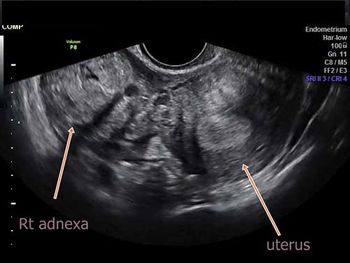

Challenge your diagnostic skills with these images from a young woman with right pelvic pain and a history of amenorrhea.